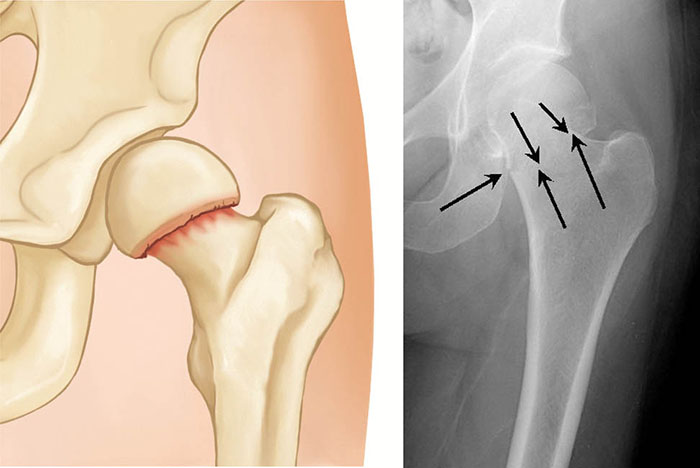

Intertrochanteric Fracture

Intertrochanteric fractures occur below the femoral neck in a broader region between the greater and lesser trochanters. The greater trochanter is the bump you feel on the side of your hip. There may be two, three, or even more fracture fragments.

two- and three-part intertrochanteric fractures

Two-part (left) and three-part (right) intertrochanteric fractures

Intertrochanteric fractures are treated surgically with either a sliding compression hip screw and side plate or an intramedullary nail.

The compression hip screw is fixed to the outer side of the bone with bone screws. A large secondary screw (lag screw) is placed through the plate into the femoral head and neck. This design allows for compression at the fracture site, increasing stability and promoting healing.